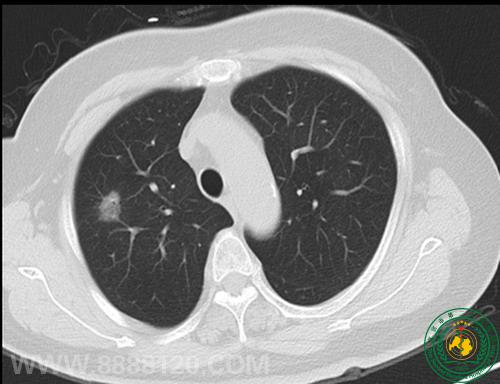

我科推出低剂量螺旋CT技样与肺癌早期筛查

我科推出低剂量螺旋CT技样与肺癌早期筛查10490